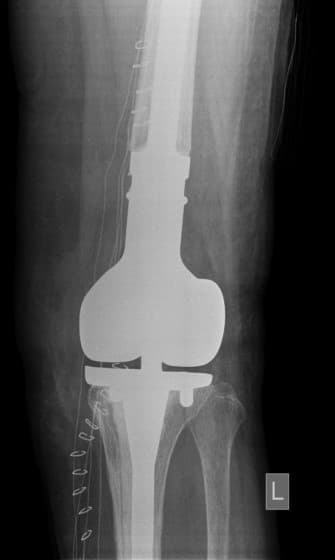

Тохиолдол танилцуулга 7.

Өвчтөн: П.Ц 60 настай, эмэгтэй 2019.1.4

Үе дайрсан ясны анхдагч хавдар, ясны дутмагшлын үед хийгдэх мэс засалimg31Үе дайрсан ясны анхдагч хавдар, ясны дутмагшлын үед хийгдэх мэс засалimg32

Зураг 1. Сэргээн засах мэс заслын өмнөх рентген зураг. Эгц урд, хажуугаас авсан байдал.

Үе дайрсан ясны анхдагч хавдар, ясны дутмагшлын үед хийгдэх мэс засалimage33

Зураг 2. Мэс заслын үеийн фотозураг. Өвдөгний хиймэл үе – сэргээн засах протез

Энэ хиймэл үений онцлог нь дунд чөмөгний гандан хэсгийн доод 1/3 хэсэг, үений булуу хэсгийг бүрэн орлох хавдрын тусгай хиймэл үе юм. Мөн hinge system-тэй.

Үе дайрсан ясны анхдагч хавдар, ясны дутмагшлын үед хийгдэх мэс засалimg34Үе дайрсан ясны анхдагч хавдар, ясны дутмагшлын үед хийгдэх мэс засалimg35

Зураг 3. Мэс заслын дараах рентген зураг. Эгц урд, хажуугаас авсан байдал.

Үе дайрсан ясны анхдагч хавдар, ясны дутмагшлын үед хийгдэх мэс засалimage36

Зураг 1. Дунд чөмөг ба шилбэ ясны 3 зэргийн дутмагшил